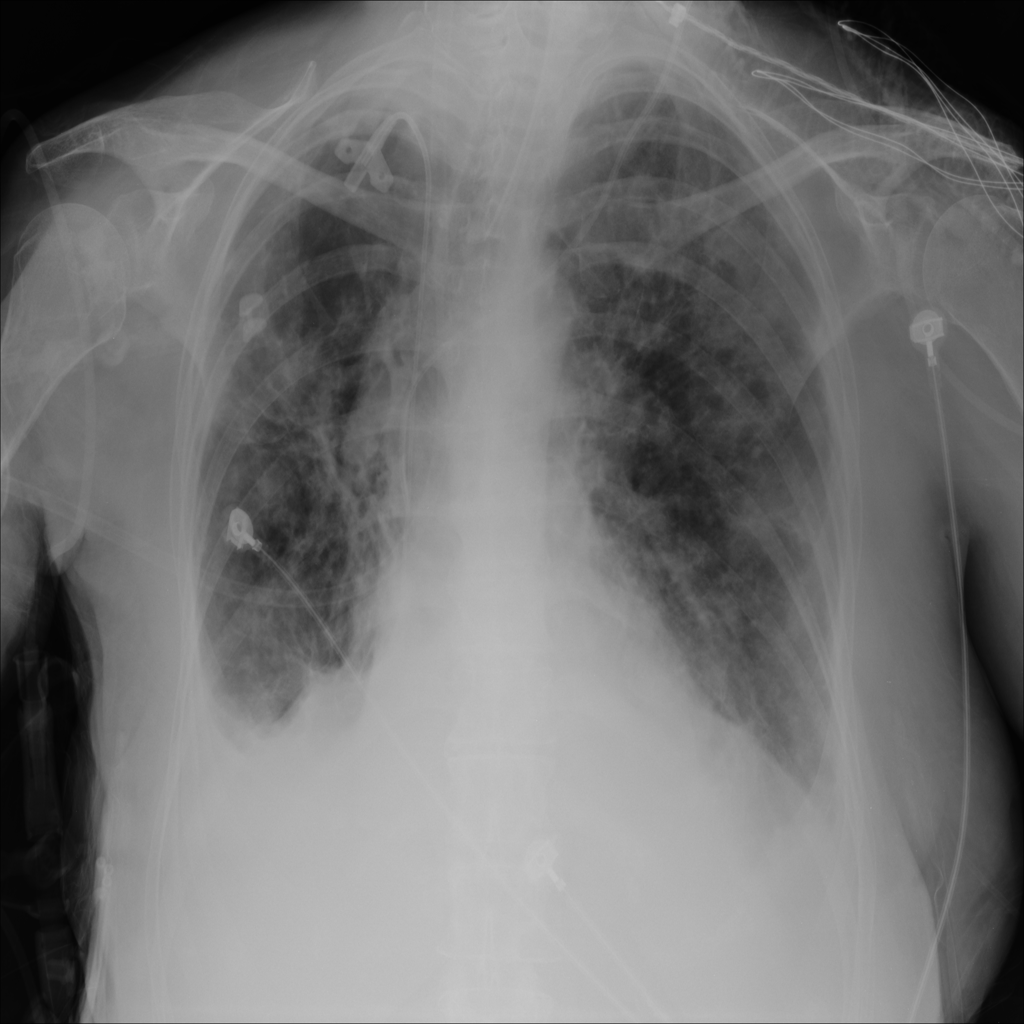

PAT-1F50 · IMG-000Fibrosis

PAT-1F50 · IMG-000

PA